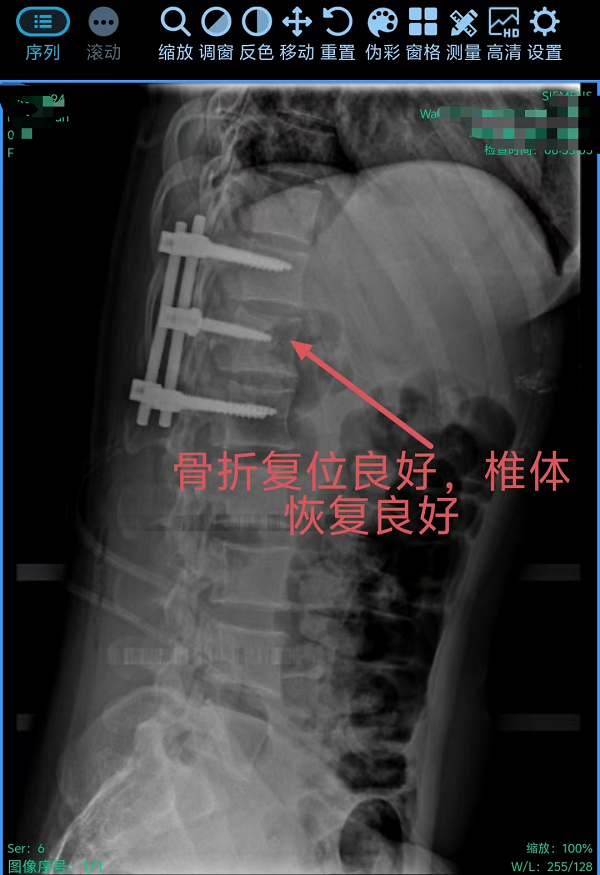

3. 为胸椎爆裂性骨折患者施后路切开复位、微创减压内固定术(四级手术),胸椎爆裂性骨折常因高能量损伤导致,骨折块可能突入椎管压迫脊髓,致残风险高。丁晔副主任医师团队采用微创理念进行减压,并完成了有效的复位与坚强的内固定,既解除了对神经的压迫,又最大程度地减少了手术创伤,为患者争取了最佳的神经功能恢复条件。

三台手术均顺利完成,患者术后恢复良好,标志着我院脊柱疾病微创化、精准化治疗迈上新台阶。